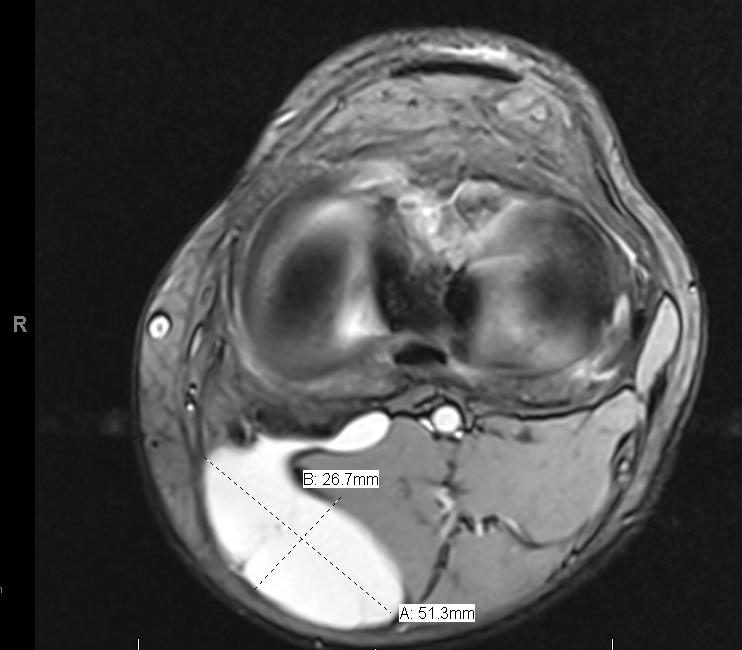

Baker Cyst Radiology Key Baker's Cyst Orthobullets A baker’s cyst is an enlarged bursa that is normally located between the medial head of the gastrocnemius and a capsular reflection of the semimembranosus, named oblique popliteal ligament. Popliteal cysts are common soft tissue masses in children that unlike the adult population, are most often not associated with. They typically result from a problem inside the knee joint, such. Baker's Cyst Orthobullets.